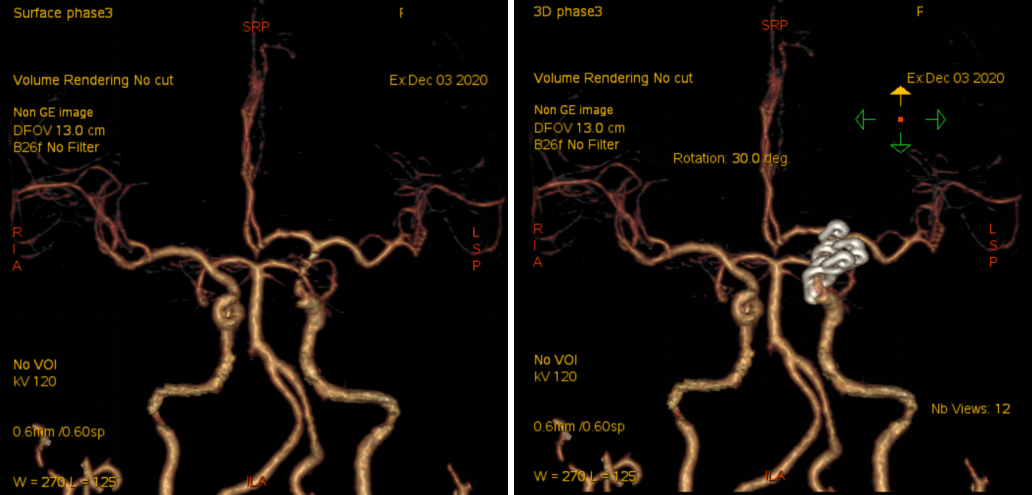

入院后予完善头颅DSA检查提示左侧颈内动脉眼动脉段动脉瘤;头颅MR提示脑内多发陈旧梗死,告知其介入栓塞、开颅夹闭等治疗方式、利弊、风险及费用等,患方商量后决定行开颅动脉瘤夹闭术。

头颈部CTA

术前DSA